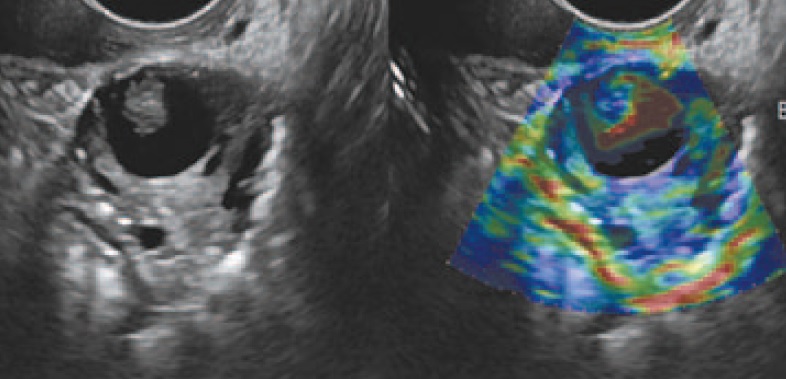

Пациентке Ф. 34 лет по данным УЗИ был установлен диагноз опухоли правого яичника. При этом обнаружено: правый яичник размером 4,2×2,2 см, в структуре определяется многокамерное тонкостенное жидкостное образование размером 2,9×2,0 см, в одной из камер определяются пристеночные солидные компоненты до 0,8 см. Левый яичник размером 2,4×1,7 см, структура неоднородная, с солидным компонентом 1,3×1,4 см. Свободной жидкости и дополнительных объемных образований в малом тазу не выявлено. Пациентке по месту жительства выполнена операция в объеме резекции яичников. При гистологическом исследовании обнаружена серозная папиллярная цистаденома пограничного типа. Больная находилась под наблюдением. При очередном УЗИ через 9 мес после первой операции в яичниках выявлены солидно-кистозные образования с пристеночной шероховатостью (рис. 5).

Рис. 5. Ультразвуковая томограмма яичника. На изображении неувеличенный яичник. В его структуре тонкостенное кистозное образование с прозрачным анэхогенным содержимым и пристеночными солидными папиллярными разрастаниями.

Fig. 5. Ultrasound ovarian tomography. The ultrasound image showing the normal sized ovary. The structure of the ovary contains thin-walled cystic lesion with clear anechoic contents and wall solid papillary growth pattern.